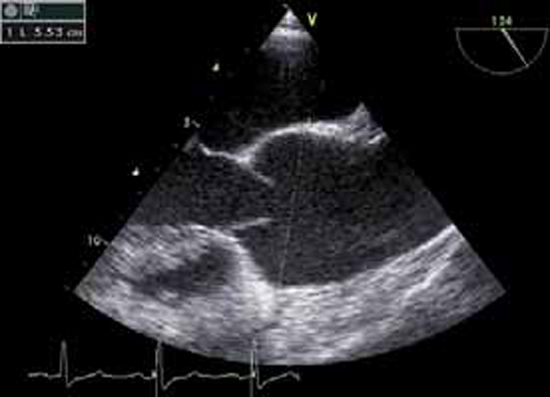

• aspect des valves, remaniées ou non, calcifiées ou non, bi- ou tricuspides (figure 4),

Figure 4 : Orifice aortique bicuspide en ETT (bicuspidie horizontale), avec petite IA commissurale au doppler couleur